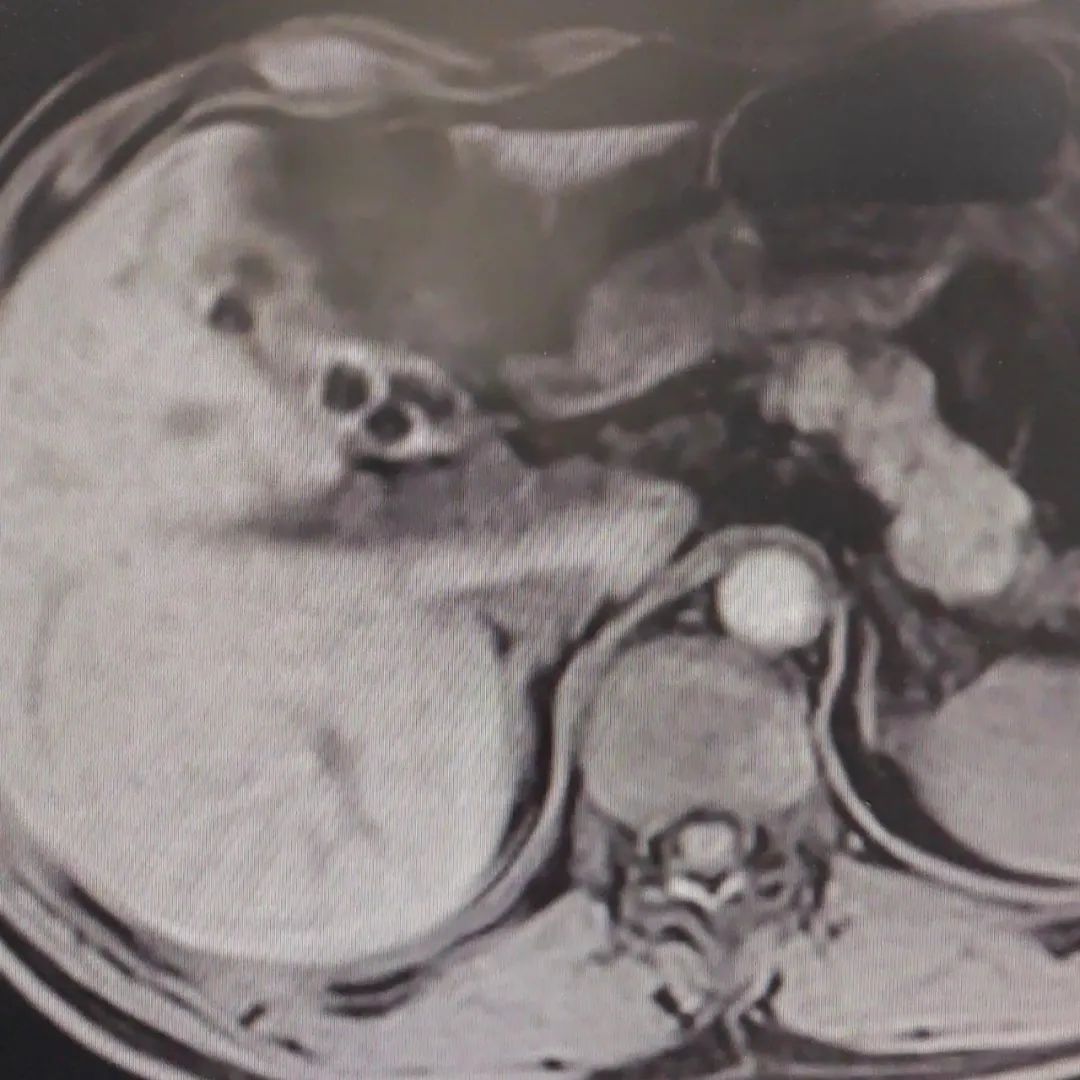

在当地医院检查后,小薇确诊胆囊充满型结石。影像可见,她的胆囊里密密麻麻地长满了结石,数量有上百颗。